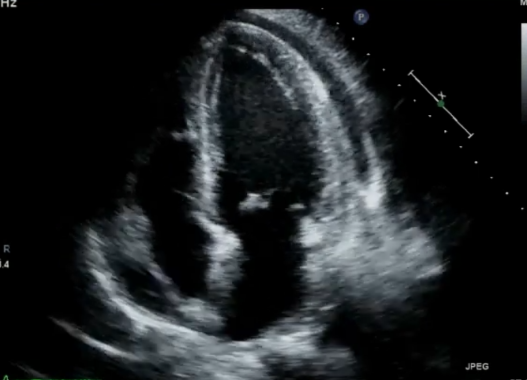

Parasternal Long-Axis (PLAX)

The parasternal long axis gives you the descending aorta which is the single best landmark for distinguishing pericardial from pleural fluid.

Fluid posterior to the aorta → pleural.

Fluid anterior to the aorta → pericardial.

pericardial effusion on parasternal long axis plax